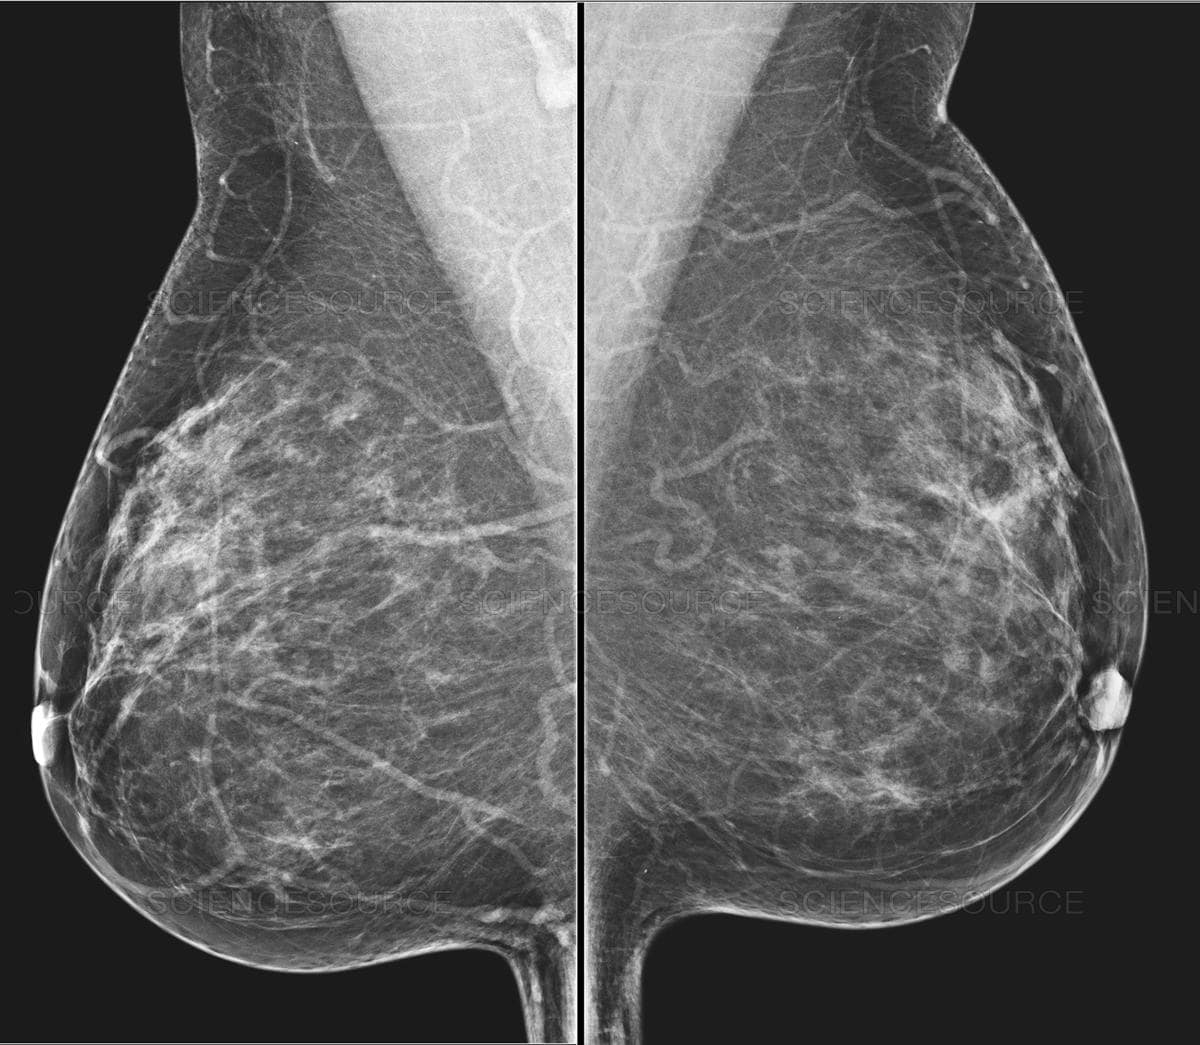

– Tessék derékig levetkőzni. Lépjen közelebb. Hajoljon kicsit le. Ne dugja a képbe a karját. Az állát fordítsa el. Most eressze le a vállát. A testével forduljon a fal felé. Dőljön előre kicsit. Fogja meg a másik kezével a rudat. Ne mozogjon. Nem jó, homályos lett, még egyszer. Ja, ezt itt el lehet forgatni. Ez egy új gép, most tanuljuk mi is. Most a másikat. Azt hittem, ez majd jobban megy. Ne rogyassza be a térdét. Húzza ki magát. Most dőljön a gép felé, és forduljon, ahogy az előbb, csak fordítva. És kicsit hajlítsa be a térdét. Öltözzön fel és üljön le kint.

– Vetkőzzön le a függöny mögött derékig. Mindent hagyjon ott. Adok lábzacskót. Adja ide a régi felvételeit. Nézzük. Ez a bal, ez a jobb. Feküdjön le. Nem, fordítva. Ez mikori? Mondtam, hogy feküdjön le. A régi CD-jét nem tudjuk beolvasni, új a gép. Ma dolgozunk vele először. Aha, ide vetíti a balt, ide a jobbat. Nem, először a bal két felvételét, aztán a jobbét együtt, összerakja. Feküdjön már le, mit nézeget. Látod, ez a kettő jön fel először. Na nézzük. Feküdjön hanyatt. Forduljon felém. Úgy, nagyon jó. Készen vagyunk. Ezt kiveszem maga alól, ezzel megtörölközhet.

kép | healthimaging.com